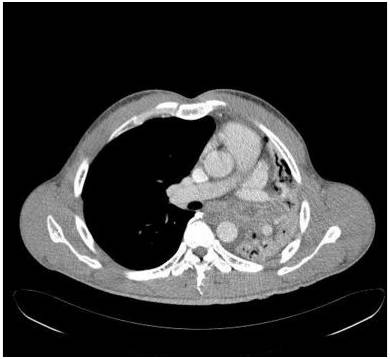

胸部前后位示弥漫不均匀的异常密度影,左肺体积缩小,左肺门区肿块样影与心膈角呈钝角。未增强纵隔窗CT示左肺肺不张,左主支气管完全受阻。增强CT示左主支气管及其段支气管内非强化的肿块。最小密度投影示左肺叶远端支气管重度狭窄,左主支气管及以下层面受阻。